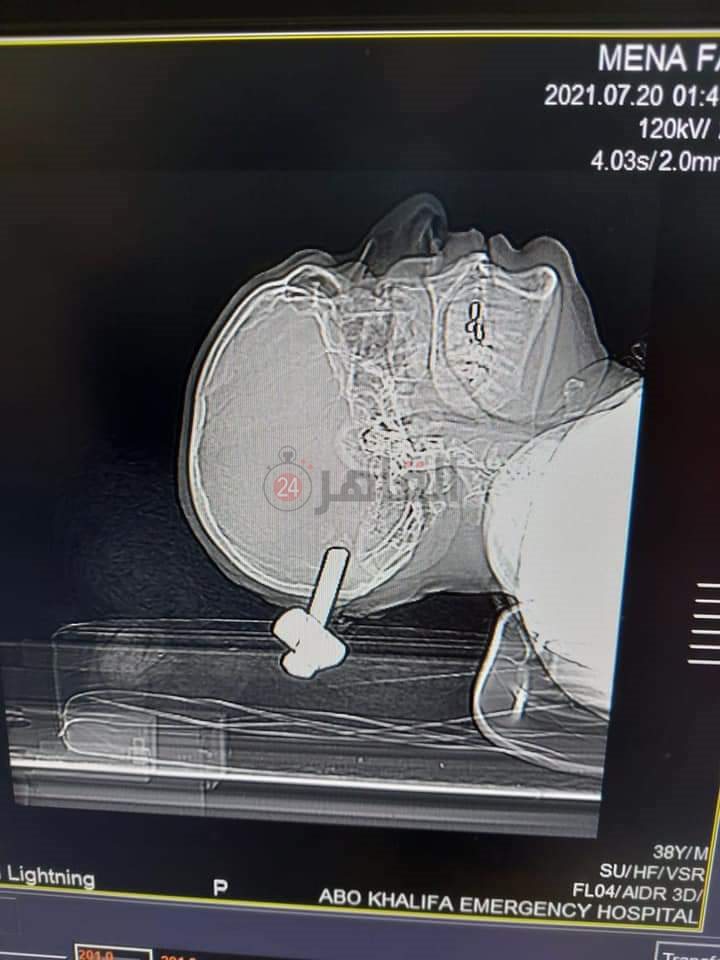

استخراج مسمار سيارة نقل من جمجمة مريض بمستشفى أبو خليفة في الإسماعيلية (صور)

كشفت مصادر طبية بصحة الإسماعيلية، عن نجاح الفريق الطبي بمستشفى أبو خليفة الطوارئ، الكائن بطريق الإسماعيلية بورسعيد، في استخراج مسمار كاوتش نقل ثقيل من جمجمة مريض، اندفع مخترقا عظام الجمجمة ليستقر في العظام القفوية للجمجمة.

وأكدت المصادر أن العملية استغرقت 4 ساعات، مشيرة إلي خروج المريض بعد الجراحة بدرجة الوعي كاملة وحالة مستقرة.